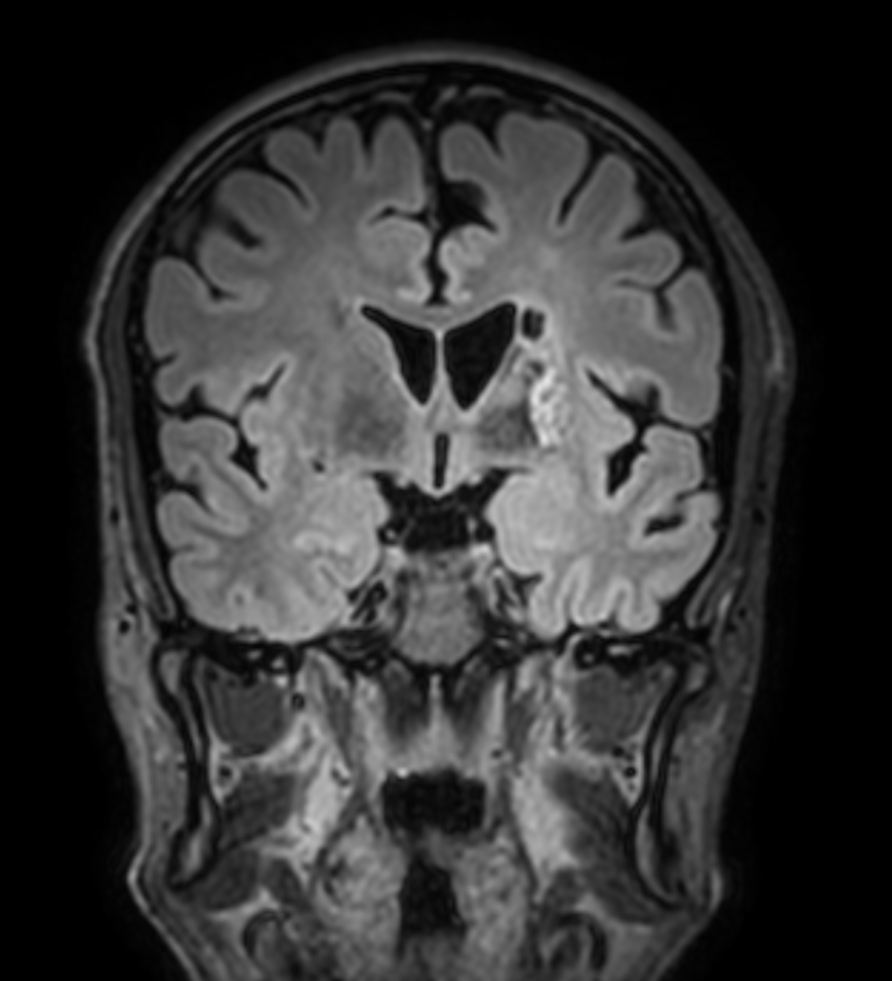

3D VIEW - T2w FLAIR

-